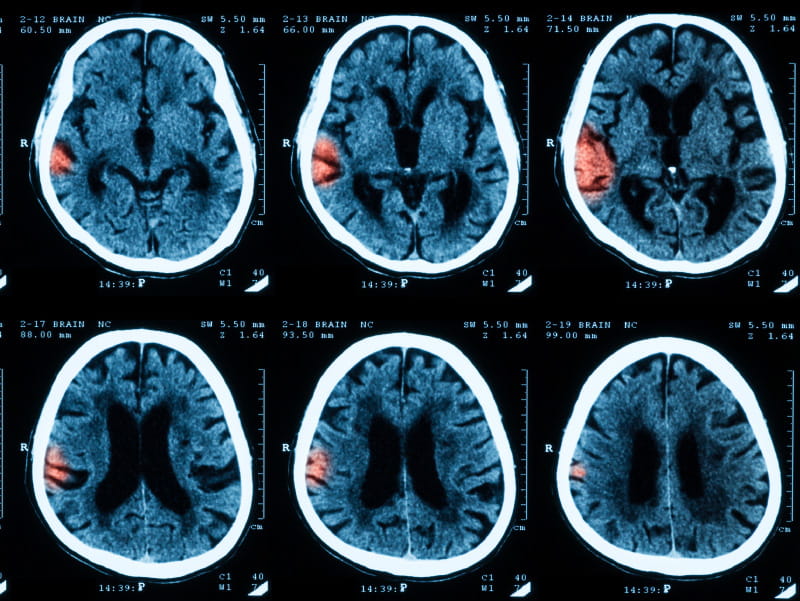

Black women in their 50s may have more than triple the risk of stroke compared to white women of the same age, according to a new study that also found a healthy lifestyle could help curb much of that risk.

After a median 13 years, strokes had occurred in 410 black women and 3,934 white women. Overall, black women had a 47 percent higher risk for stroke than white women, regardless of age. The risk was highest among black women in their 50s, who had a 3.5-fold increased risk compared to white women of the same age.

Yet, the racial gap in stroke risk across all age groups seemed to disappear when researchers accounted for stroke risk factors, including high blood pressure, weight, smoking, exercise and use of hypertension and cholesterol medications. For black women in their 50s, stroke risk fell considerably but remained higher compared to their white counterparts.